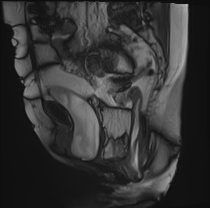

矢状位动态扫描

排便动态扫描

研究显示,患者排便时盆底整体下降异常,肛提肌裂孔异常增宽。

可见肛直肠交界处严重异常下降。

可见直肠肛门内套叠,直肠折叠入肛管。另可见少量直肠前膨出。

可见中度膀胱膨出。

可见轻度阴道脱垂。

子宫未显影——子宫切除术后状态。